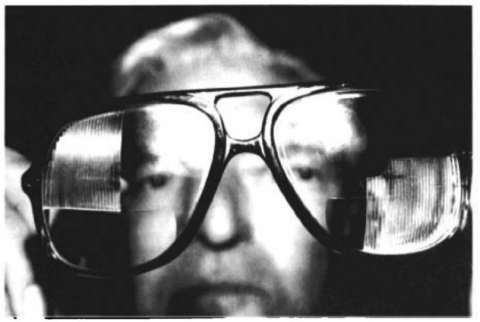

The new implementation for electronic and even AI devices has proven helpful in some cases with visual field defects, but it has not been well studied on cross-quadrant HH. A study tested the efficacy of glasses with MRG in patients with Homonymous Hemianopia and the overall findings were that even when the walking was slower the patients would pay more attention and have a minimal increase in ambulation.[12]

Some studies have recommended "checkerboard prisms." The goals of prisms are to expand the intact visual field. Images that normally fall on the hemianopic retina are shifted so they become visible by the seeing portion of the retina. The use of these prisms has been reported with varying degrees of success. "[1]